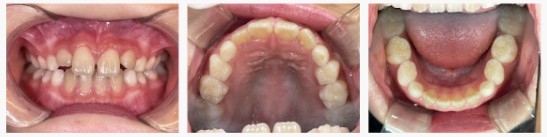

▼After(治療後)

治療を終える頃には、上の前歯の突出が改善し、自然に口を閉じられるようになりました。

横顔のバランスも整い、笑顔の印象がより柔らかくなりました。

また、口呼吸が減り、舌の位置も安定。